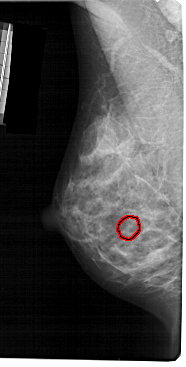

FILE: A_1392_1.LEFT_CC.OVERLAY

TOTAL_ABNORMALITIES 1

ABNORMALITY 1

LESION_TYPE CALCIFICATION TYPE PLEOMORPHIC DISTRIBUTION CLUSTERED

ASSESSMENT 4

SUBTLETY 2

PATHOLOGY BENIGN

TOTAL_OUTLINES 1

BOUNDARY

LEFT_CC LINES 5386 PIXELS_PER_LINE 2731 BITS_PER_PIXEL 12 RESOLUTION 43.5 OVERLAY